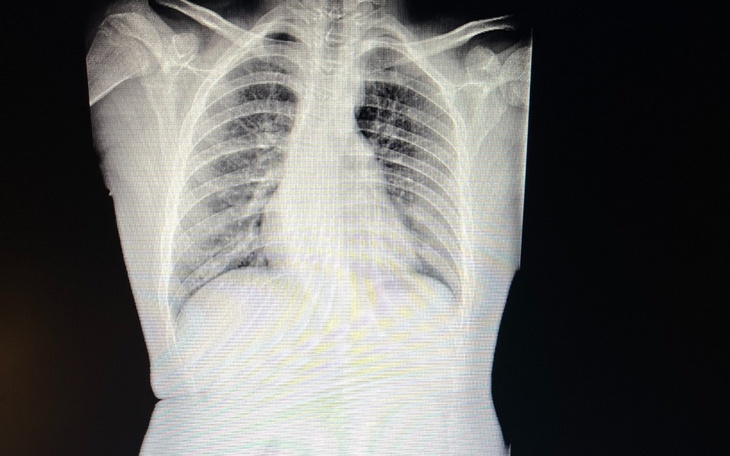

Mój jedenastoletni syn Rysiu cierpi na zaawansowaną skoliozę kręgosłupa. Na ten moment choroba przekroczyła możliwości leczenia za pomocą gorsetu oraz rehabilitacji. Rysiu jest w wieku, w którym cały czas rośnie, a schorzenie to może bardzo gwałtownie wpłynąć na jego dalsze życie. Występujące u niego skrzywienie kręgosłupa, które prawdopodobnie wynika z bardzo szybkiego wzrostu (mierzy 185 cm w wieku 11 lat) jest tak głębokie, że w przyszłości grozi ciężkimi dolegliwościami bólowymi oraz ograniczeniem sprawności, w stopniu, który może doprowadzić do kalectwa.

Zabieg ten należy przeprowadzić dość szybko, gdyż jest skuteczny tylko w odniesieniu do organizmu w okresie wzrostu, w przedziale wieku pomiędzy 8 a 16 lat, a także pod warunkiem, że mierzone w stopniach skrzywienie kręgosłupa (które w miarę upływu czasu się pogłębia) nie przekroczy granicznej wartości 65 stopni.